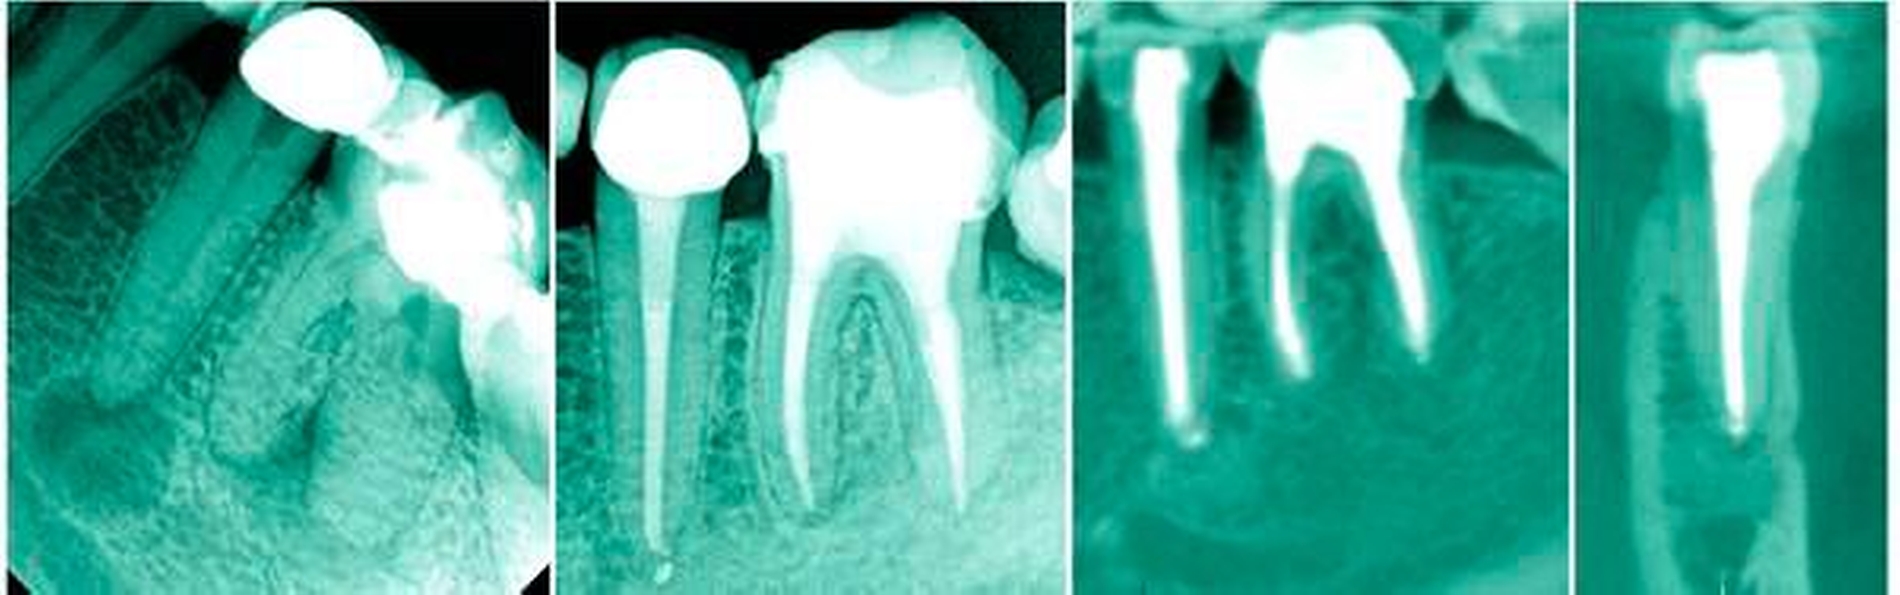

Der zweite untere Prämolar hat noch öfter eine Wurzel als der erste untere Prämolar (etwa 99,6 Prozent der Fälle) [Cleghorn et al., 2007b]. Zwei und drei Wurzeln sind hier sehr selten (0,3 Prozent beziehungsweise 0,1 Prozent). In der Übersichtsarbeit, die acht Studien über die Anatomie von zweiten Unterkiefer-Prämolaren zusammenfasst, ergab sich eine Prävalenz von mehr als einem Kanal in 9 Prozent aller Fälle [Cleghorn et al., 2007b]. Laut Reuver [Reuver, 2002a] scheint es beim zweiten Prämolaren öfter vorzukommen, dass bei Vorliegen eines lingualen Kanals vom Volumen her zwei gleichwertige Anteile vorliegen und die Teilung im Röntgenbild zu sehen ist. Diese Zähne sind wegen der nicht so stark ausgeprägten Abzweigung nach lingual einfacher zu behandeln (Abbildung 8).

Neben einer orthograden Aufnahme empfehlen England et al., den Tubus für eine zweite exzentrische Aufnahme im davon abweichenden Winkel von 20 Grad nach mesial oder distal auszurichten [England et al., 1991]. Martinez-Lozano et al. schlagen exzentrische Aufnahmen im Winkel von 20 und 40 Grad vor [Martinez-Lozano et al., 1999], während Rödig und Hülsmann einen Winkel von 30 Grad anraten [Rödig und Hülsmann, 2003].

In einer eigenen Untersuchung unter simulierten klinischen Bedingungen konnte ein zweiter lingualer Kanal am besten bei der Kombination eines orthograden und eines 40° mesial exzentrischen Röntgenbildes entdeckt werden [Rapsch und Paqué, 2017].